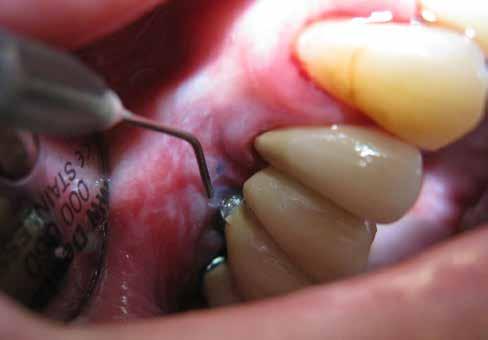

A parodontális elváltozások kezelésének elengedhetetlen része, hogy a páciens a kezelés teljes ideje alatt megfelelően együttműködjön a beavatkozásokat végző fogorvossal, és pontosan kövesse az utasításait. A megfelelő kooperáció elősegítése érdekében javasoljuk, hogy a kezelés minden fázisában egy intraorális szkenner (pl.: Condor; Biotech Dental) segítségével készült, 3 dimenziós modell segítségével ismertessük a páciensünkkel a szájüregi státuszának aktuális állapotát (2. ábra)

Az első találkozás alkalmával a kezelést igénylő terület állapotát egy intraorális szkenner segítségével rögzítjük. Ez a képalkotó eljárás kiegészíti azokat az általánosan alkalmazott vizsgálatokat, mint a radiológiai képalkotás (3. ábra) és a parodontális státuszfelvétel (4. ábra), továbbá hozzájárul a pontos diagnózis felállításához.

Abban az esetben, ha előrehaladott állapotban lévő fogágybetegség kezelését végezzük, azaz 5 mm-es, vagy annál nagyobb tasakmélységet mértünk, akkor a számunkra kívánatos változások elérése érdekében egy második tisztítási fázis elvégzésére is szükség van. Ehhez egy 980 nm-es hullámhosszon, 10 W-os teljesítmény mellett alkalmazott diódalézert is használhatunk, amely nem csak szájsebészeti célú alkalmazásra, hanem a parodontális elváltozások kezelésére is alkalmas lehet.

A második szakaszban a protokollnak megfelelően végzett kezelés során egy PRIMO diódalézert (MEDENCY, 9. ábra) alkalmazunk. A beavatkozás során 10 mm hosszú 400 μ széles, egyszer használatos fényvezető szálakat használunk. A készüléket az alábbi paramétereknek megfelelően állítjuk be: pulzus modalitás 30/70; 2,4 W teljesítmény; 25 másodperc működési idő. Ezek a beállítások szükségesek ahhoz, hogy a gyökérfelszínt nagy mélységben is meg tudjuk tisztítani, és a

A diódalézerek alkalmazása esetén szignifikánsan nagyobb mértékben csökken a baktériumok száma, mint amikor a kezelés során nem alkalmaznak lézereket. Lézerek alkalmazása esetén a kezelt esetek 96,6%-ánál megfigyelhető volt a vérzési index javulása, míg a hagyományos módszerekkel kezelt páciensek esetében csupán a betegek 66,7%-ánál lehetett ugyanezt megfigyelni. A parodontális tasakok mélysége ugyancsak szignifikánsabb mértékben csökkent lézerek alkalmazása esetén.